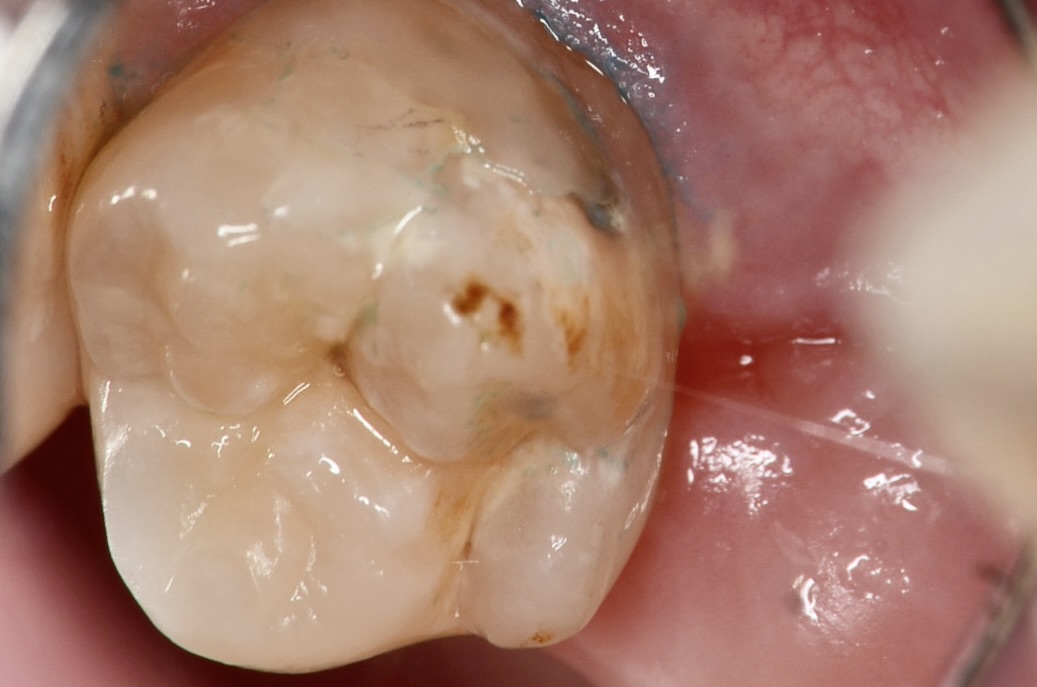

上顎7番頬側面観

歯ブラシがしにくい上の奥歯の横は、虫歯ができやすい場所でもあります。 -

かつてレジンで治療されている部分が虫歯になっています。 -